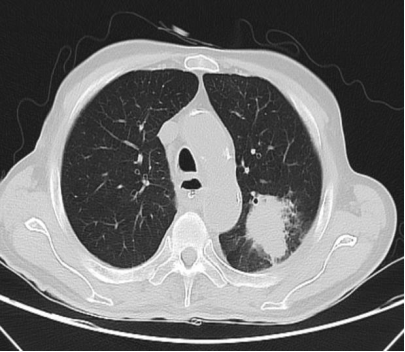

胸部CT示(图1):左肺上叶占位性病变,考虑肺癌可能,胃窦部胃壁增厚并异常强化;6月27日电子胃十二指肠镜示(图A、B、C):胃角、胃窦变形,表面发红、粗糙、肿胀,局部可见深凹陷溃疡病变,近幽门宫腔狭窄,镜身无法通过。